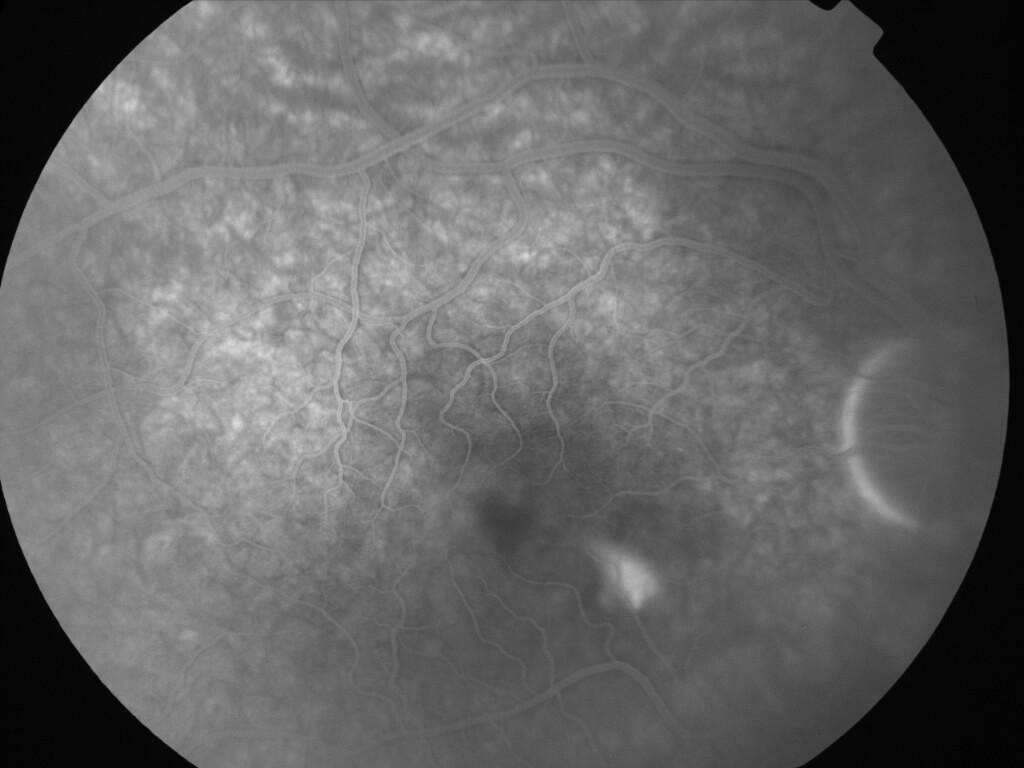

CHORIORETINOPATHIE SEREUSE CENTRALE

IM000005.jpg